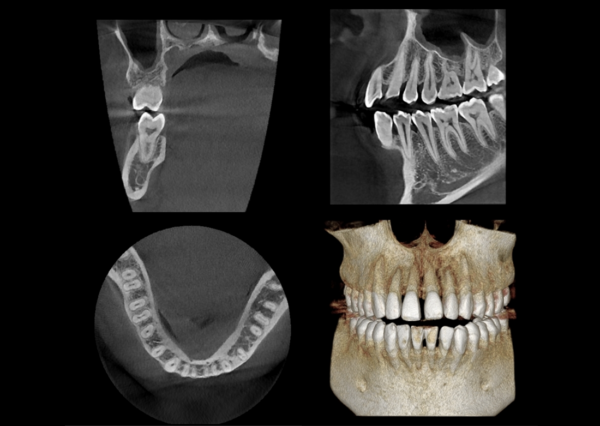

Thay vì phải dự đoán, Papaya 3D Plus trao cho Bác sĩ quyền kiểm soát hoàn toàn ca điều trị thông qua các công nghệ cốt lõi:

Tùy chọn đa vùng chụp (Multi-FOV): Linh hoạt thay đổi trường nhìn từ nhỏ đến lớn, phục vụ đích đáng cho từng chỉ định lâm sàng, hạn chế tia X dư thừa.

FOV trung bình (8×8, 14×8): Hoàn hảo cho cấy ghép Implant toàn hàm, nhổ răng khôn ngầm.

FOV lớn (16×14): Dành riêng cho phẫu thuật hàm mặt, chỉnh nha toàn diện.

Cảm biến Flat Panel Detector (CMOS): Thu nhận hình ảnh sắc nét đến từng Voxel, giảm thiểu tối đa hiện tượng nhiễu tán xạ (Artifact) từ các phục hình kim loại cũ trong miệng bệnh nhân.

Cho phép Bác sĩ cắm trụ Implant ảo (Virtual Placement), vẽ ống thần kinh và xuất file báo cáo lâm sàng trực quan.

Hình ảnh 3D sống động giúp bệnh nhân dễ dàng hiểu được tình trạng bệnh lý của mình, từ đó tăng tỷ lệ đồng ý tiếp nhận điều trị (Case Acceptance Rate).